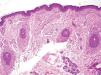

Presentamos el caso de una paciente de 16 años de edad, sin antecedentes personales de interés, que consultó por una lesión localizada en el párpado inferior del ojo derecho que estaba presente desde el nacimiento. Se trataba de una placa de 1cm × 0,5cm aproximadamente, mal delimitada, homogénea, sin orificios ni comedones en su superficie, de color de piel normal y de aspecto aterciopelado (fig. 1). La lesión era asintomática y su evolución había sido siempre estable, sin cambios bruscos en su tamaño, forma o aspecto. Se practicó un punch-biopsia de 4mm en el centro de la lesión, donde se pudo observar una neoplasia de diferenciación folicular. Se realizaron cortes seriados de toda la biopsia y en todos ellos se observó una proliferación de folículos pilosos maduros en similar estadio de diferenciación, localizados en zonas altas de la dermis reticular, inmersos en un estroma densamente celular (fig. 2). La vaina de tejido conectivo de todos los folículos presentaba un llamativo engrosamiento fibroso (fig. 3). No se encontró en toda la muestra ninguna cavidad quística central. Con las características clínicas y los hallazgos histológicos la lesión se diagnosticó de nevus del folículo piloso. Como la lesión era asintomática y a la paciente no le preocupaba desde el punto de vista estético, se decidió no extirparla y se le aconsejó consultar cualquier cambio que notara.

Desde el punto de vista histológico se caracteriza por la proliferación en la parte alta de la dermis de folículos pilosos generalmente de pequeño tamaño, con un engrasamiento fibroso perifolicular, rodeados de un estroma altamente celular. En ocasiones se pueden encontrar glándulas sebáceas, glándulas ecrinas o fibras musculares, lo que motiva a considerar al nevus del folículo piloso como un auténtico hamartoma1,3.